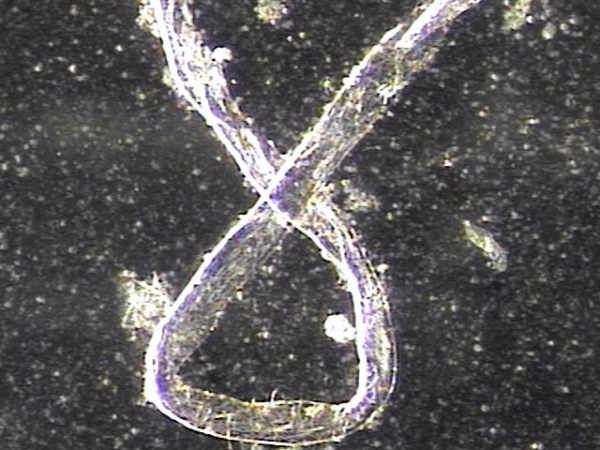

주 2회 전립선과 정낭 그리고 정관등의 표적 치료중 정관을 막고 있는 거짓중층원주상피세포와 사정되지 못한 정자들과 단백질등의 치료된 현미경학적 자료입니다.

This microscopic image was taken after repeated targeted treatment.

It shows that old cells, proteins, and sperm had collected and blocked the vas deferens.

The size of this material confirms that it was stuck inside the vas deferens.

The treatment helped to remove this blockage, allowing the ducts to open and improving the flow of semen.

사진 속 현미경 영상은 정관에서 배출된 치료 후 내용물로 보입니다. 관찰되는 소견을 근거로 말씀드리면:

-

길게 뻗은 섬유성 구조와 세포성 잔여물이 함께 보입니다.

이는 흔히 노화된 거짓중층원주상피세포, 단백질 덩어리, 또는 정자와 점액질이 엉겨 붙은 물질일 가능성이 높습니다.

직경이 비교적 크고 길게 뭉친 형태를 띠기 때문에, 정관 내강을 막아 정액의 흐름을 방해했을 것으로 추정됩니다.

즉, 정관을 막고 있던 주된 원인은

오래된 상피세포 찌꺼기, 단백질 응집물, 그리고 사정되지 못하고 고여 있던 정자들이 엉겨 형성된 덩어리(blockage material) 로 보입니다.

This microscopic image shows material that was removed after targeted treatment of the vas deferens.

The findings suggest that the blockage was mainly caused by:

- Old cells that had shed from the lining,

- Protein debris, and

- Sperm that could not be released and became trapped.

These substances clumped together over time and formed a plug large enough to block the vas deferens, preventing normal flow.

The treatment helped clear this material, allowing for better passage through the duct.